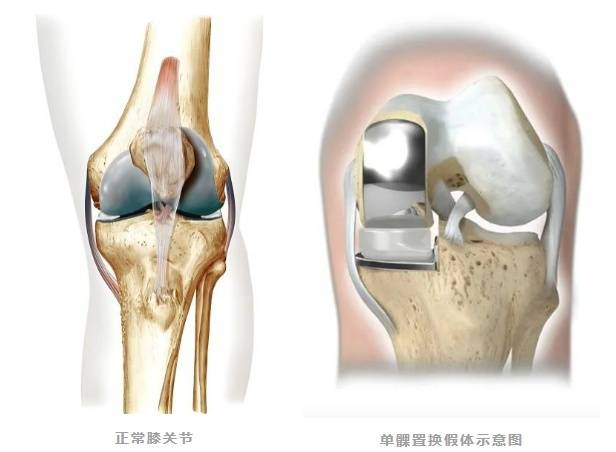

▲膝关节单髁置换术前术后 保留健康组织的治疗理念 膝关节单髁置换术通过微创技术仅置换病变严重的单侧间室(内侧或外侧),这种“精准定位”的治疗方式,能够尽可能保留患者健康的骨组织、韧带及本体感觉,手术创伤相对较小。术后患者疼痛可得到缓解,膝关节的自然活动功能得以保留,步态恢复更趋向自然协调。 多学科协作优化恢复流程 快速康复外科理念贯穿于治疗全程,为患者提供标准化、个性化的康复路径。术前进行全面评估和健康宣教,帮助患者做好身心准备;术中采用精细化操作,减少组织损伤;术后早期康复师介入指导功能锻炼。这种多学科协作模式有助于缩短住院时间,多数患者能在短期内达到出院标准,更快回归家庭生活。 护理团队实施全程化健康管理,从入院到出院后随访,提供涵盖疾病知识、康复锻炼、居家护理等全方位指导。针对患者术后可能出现的心理压力,医护人员可提供专业心理疏导,帮助建立积极康复的信心。 个性化方案助力功能恢复 膝关节功能的良好恢复,离不开科学系统的康复训练。专业医疗团队会为患者量身定制康复计划:早期进行关节活动度训练,防止粘连;中期强化肌力训练,增强关节稳定性;后期优化步态训练,提升活动协调性。通过循序渐进的康复锻炼,多数患者能够恢复日常活动能力,完成行走、上下楼梯等动作。 微创技术的临床应用优势 膝关节单髁置换术的临床应用特点包括:手术切口较小,术后疼痛轻,恢复时间短;保留更多自身组织,关节活动更接近自然状态;术后并发症风险低,康复效果稳定。临床实践中,患者在疼痛缓解、关节功能恢复及生活质量改善等方面可获得良好反馈。 健康提醒 当膝关节疼痛严重影响生活质量时,及时寻求专业医疗帮助至关重要。通过精准微创技术、快速康复流程和个性化护理方案,膝关节单髁置换术为患者提供了一种重获行动自由的可能。科学应对膝关节炎,才能让生活回归轻盈与活力。 关节骨病科简介 基本概况 我院关节骨病科现开放床位32张,汇聚了16名经验丰富、技术精湛的专业医护人员。科室以关节疾病诊疗、运动医学修复、骨病外科治疗为核心发展方向,深耕骨关节疾病、运动损伤、病理性骨折及骨科肿瘤等领域,为患者提供全方位、个性化的精准医疗服务。 诊疗技术 关节置换与翻修:早期股骨头坏死保髋术,人工股骨头/全髋关节置换术,髋关节翻修术,膝关节单髁置换/表面置换术,膝关节翻修术,人工肩关节置换术。 关节镜微创技术:关节镜下膝关节前后交叉韧带重建术,半月板缝合/成形术,关节内骨折镜下复位内固定术,肩袖修复术,肩关节不稳修复术,肩峰成形术,踝关节镜下韧带修复重建术。 骨肿瘤综合治疗:四肢骨肿瘤切除重建(含关节置换),骨肿瘤保肢术、化疗术。 其他骨病治疗:骨结核病灶清除植骨术,同种异体骨移植,各类病灶清除术,肢体矫形修复术。 专家简介 周仁实 主任医师、副院长。 1996广东医科大学临床医学本科毕业,从事骨科临床工作20多年。发表SCI论文1篇(通信作者),国家级省级论文10多篇。社会兼职:广东省医学教育委员会脊柱专业委员会副主任委员,广东省医师协会理事等。 擅长领域:擅长脊柱内固定、脊柱微创、骨肿瘤、关节置换、关节镜等技术,熟悉掌握骨科常见病与多发病的诊断与治疗。 欧阳思强 骨外科主任医师,关节骨病科主任。 广东省医师协会骨关节外科医师分会委员。2003年毕业于广东医学院临床医学系,毕业后一直从事骨科工作,曾先后到南方医科大学附属南方医院、广东省中医院进修。 擅长领域:擅长关节、骨病,运动损伤等疾病的诊断治疗;熟练掌握人工关节置换、人工关节翻修、骨关节病治疗,以及运动损伤疾病的关节镜下手术治疗等。 李远志 中西医结合医学副主任医师,关节骨病科副主任,硕士研究生学历。 2009年毕业于福建中医药大学,曾先后到河南省洛阳正骨医院、广州中医药大学一附院骨关节病科进修学习。 擅长领域:擅长关节、脊柱、骨病等中西医结合治疗。 黄平 骨外科主任医师。 曾到广州南方医学院创伤骨科进修学习。 擅长领域:擅长骨关节病、骨肿瘤的诊治;熟练掌握各类长骨骨折手法复位及切开复位内固定治疗术,骨盆骨折切开复位内固定术、断肢再植术、各类创面修复术;能主刀完成人工全髋关节置换、人工膝关节表面置换手术,掌握了髋关节、膝关节翻修技术。 苏中南 骨科主治医师。 2012年毕业于三峡大学临床医学系。曾到暨南大学附属第一医院进修学习关节、运动医学专业。 擅长领域:熟悉人工关节置换、关节镜的检查和治疗,擅长关节、骨病、运动损伤、脊柱等常见病与多发病的诊断与治疗。 王德信 中医骨伤主治医师,研究生学历。 擅长领域:熟练掌握四肢骨折正骨、运动创伤、大面积烧伤、慢性溃疡创面修复处理、关节脱位整复,四肢骨关节疾病诊治。熟悉应用内固定及外固定技术治疗各种常见骨折,能运用中西医结合、辩证运用方剂保守治疗股骨颈骨折、股骨头缺血性坏死、风湿、类风湿关节炎、髋膝关节骨关节病、老年性骨质疏松等关节骨病科常见疾病。